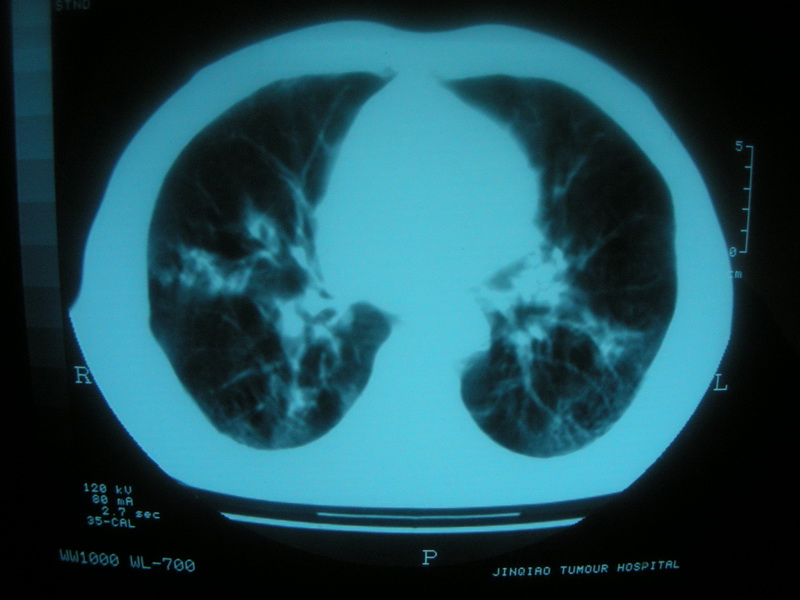

标题: CT11692:男,63岁,糖尿病史15年.抗炎治疗7天,病情 [打印本页]

标题: CT11692:男,63岁,糖尿病史15年.抗炎治疗7天,病情

请老师看看是结核还是炎症?

双肺继发性肺结核伴感染!

支持双肺继发性肺结核伴感染!

双肺继发性肺结核伴支气管播散。

考虑双肺继发性肺结核。

支持双肺继发性肺结核伴感染。